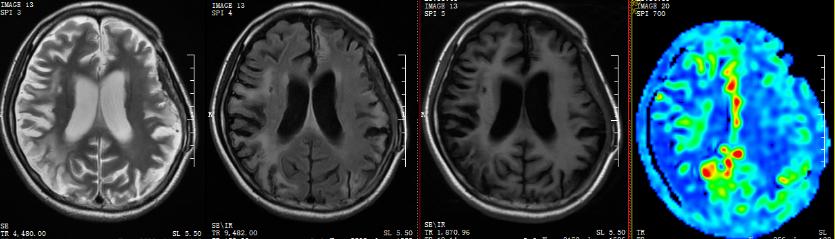

▲术前

我院ASL序列提示:双侧额颞岛顶枕叶多发片状低灌注区,以额颞顶叶低灌注较明显;DSA提示:烟雾病,双侧颈内动脉末端闭塞,颅底可见烟雾样血管生成并向远端代偿,可见右侧颈外动脉系统对颈内系统部分代偿。